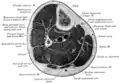

Artéria tibial anterior e os músculos e ossos da perna - vista anterior da perna direita.